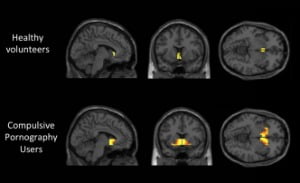

Cambridge University scientists reveal changes in brain for compulsive porn users which don’t occur in those with no such habit

People who are addicted to pornography show similar brain activity to alcoholics or drug addicts, a study has revealed. MRI scans of test subjects who admitted to compulsive pornography use showed that the reward centres of the brain reacted to seeing explicit material in the same way as an alcoholic’s might on seeing a drinks advert.

The research by Cambridge University assessed the brain activity of 19 addictive pornography users against a control group of people who said they were not compulsive users.

Lead scientist Dr. Valerie Voon, an honorary consultant neuropsychiatrist, told the Sunday Times: “We found greater activity in an area of the brain called the ventral striatum, which is a reward centre, involved in processing reward, motivation and pleasure.

“When an alcoholic sees an ad for a drink, their brain will light up in a certain way and they will be stimulated in a certain way. We are seeing this same kind of activity in users of pornography.”

1) The Cambridge study used brain scans (fMRI) to assess the activity of the reward center (ventral striatum), where cue reaction occurs in the form of dopamine spikes. This procedure is well established and has been employed in dozens of Internet addiction and other addiction studies.